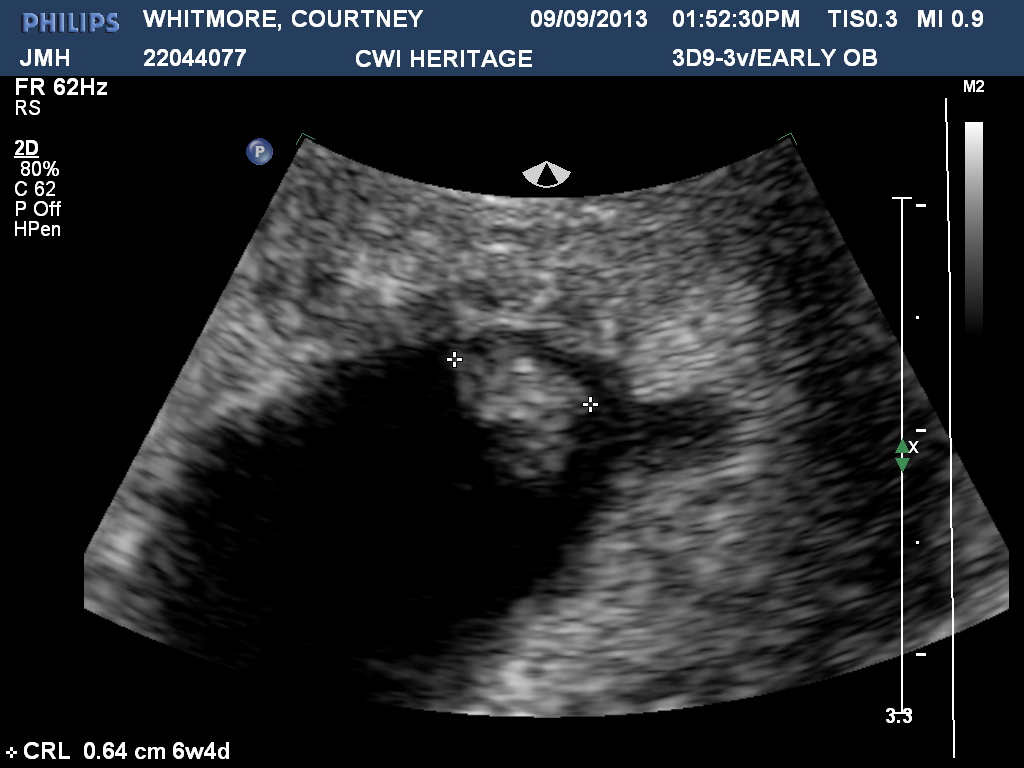

Here is my 20 week ultrasound! Any guesses?! Attachment 15779